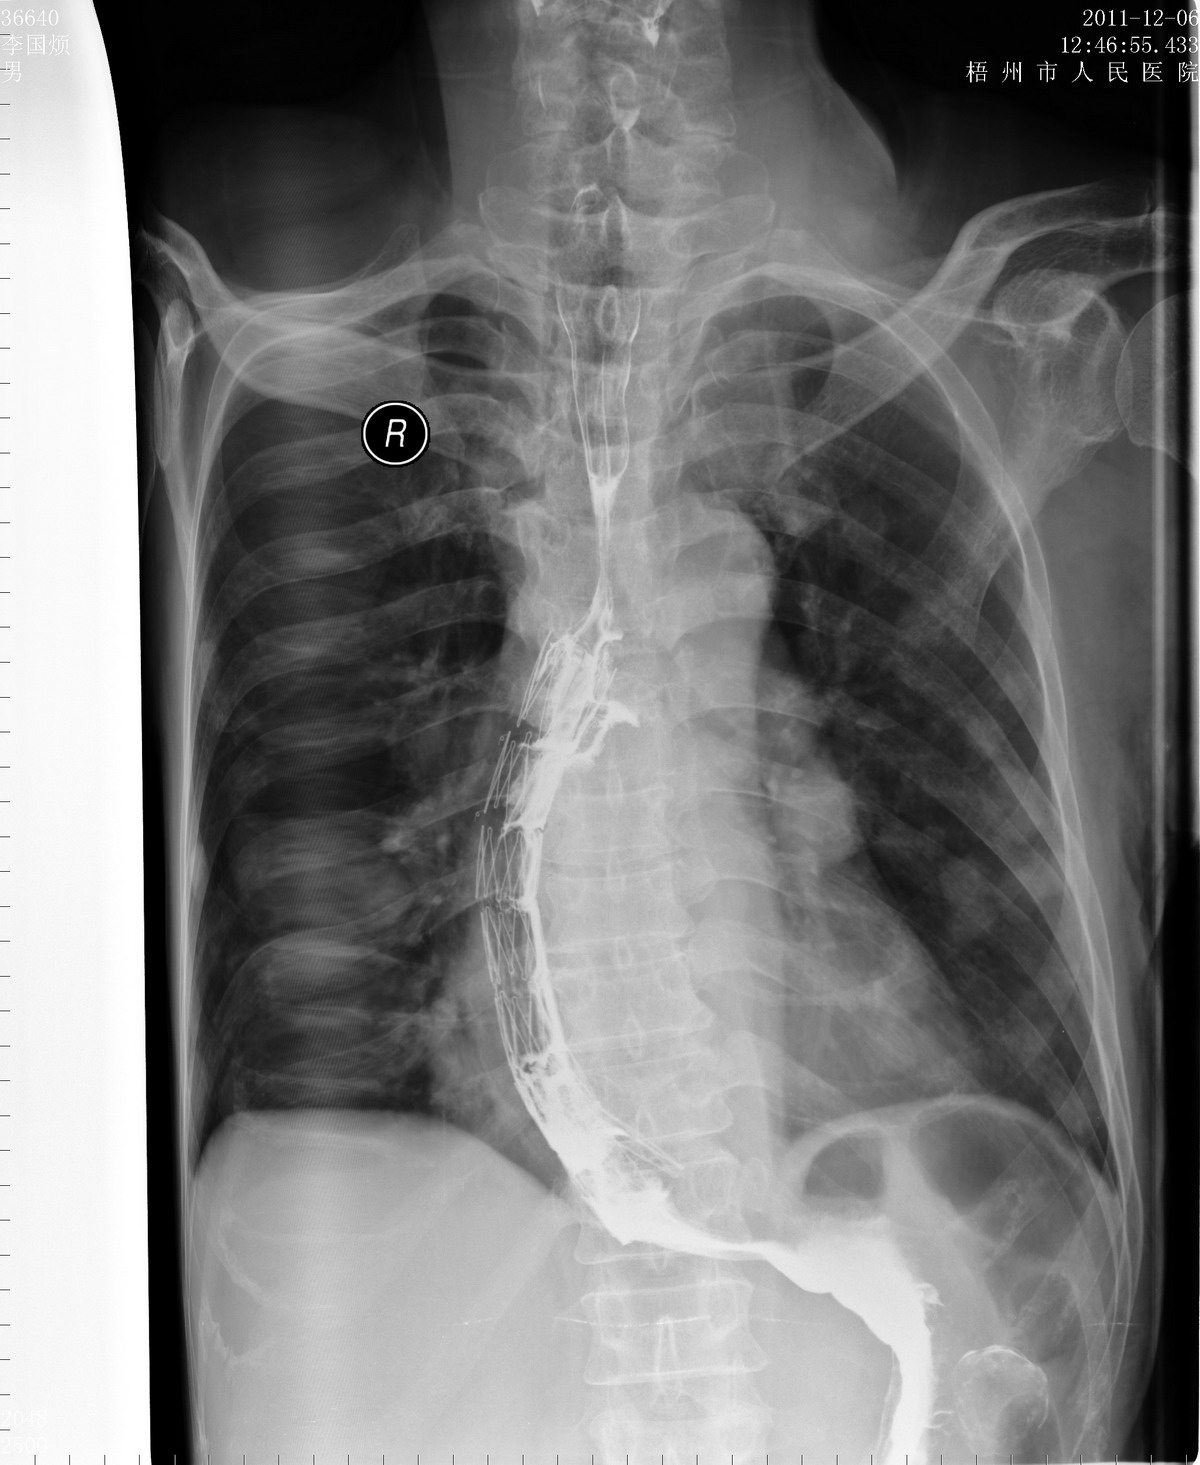

近段时间CR扫描图像右边打开不完全,而且有抖动,请教高手,QQ409787367